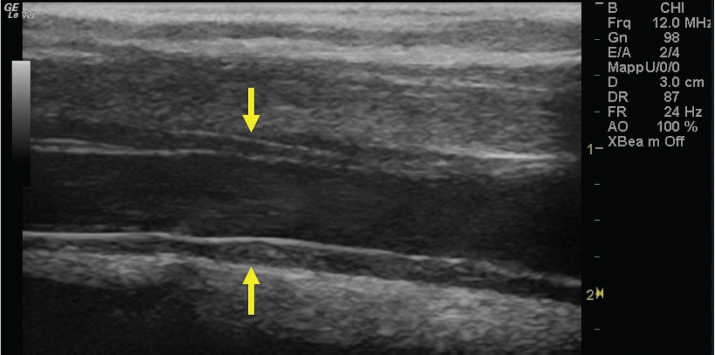

The left jugular vein appeared as an anechoic tubular structure which collapsed under the probe pressure, the color Doppler examination revealed normal blood flow within the vessel (Fig. 3). Bi-dimensional ultrasonography of the right jugular vein showed a heterogeneous, non-cavitating, hypoechoic structure occluding a narrowed right jugular vein for about 30 cm of length localized in the proximal and mid-portion of the neck compatible with a thrombus (Fig. 4). The color Doppler examination showed blood flow through the lateral portions of the thrombus in the cranial and mid-portions of the right jugular vein (Fig. 5). Cranially to the thrombus, a marked distension of the maxillary and linguofacial veins was evident, with a turbulent and echogenic flow; the latter was compatible with blood stasis near the thrombus (Fig. 6). Caudally to the thrombus, the right jugular vein presented reduced diameter, thickened walls, and normal blood flow (Fig. 7). The cranial part of the thrombus originated from a heterogeneous scare tissue, localized at the level of the right mandibular angle (Fig. 8). After injection of the first saline contrast bolus in a right facial vein, no microbubbles appeared in the right jugular vein, caudally to the thrombus, proving the presence of a complete right jugular vein occlusion. On the contrary, after injection of the second bolus, microbubbles were visualized in the left jugular vein as small, intense, echo signals within the vein lumen, demonstrating the presence of collateral circulation that drained the blood from the right facial veins to the left jugular vein (Fig. 9). Venography results confirmed the complete occlusion of the right jugular vein and the presence of submandibular venous collaterals that connected the right facial veins with the left jugular vein (Figs. 10 and 11). Based on the previous results, the diagnosis of JVT with complete occlusion of the vessel lumen was confirmed. The horse’s owner refused any proposed medical or surgical therapy.

Fig. 4. Bi-dimensional ultrasonographic image of the right jugular vein in longitudinal section. The lumen of the vessel was occluded by a heterogeneous, non-cavitating, hypoechoic structure compatible with a thrombus (arrows).ç

Fig. 7. Bi-dimensional ultrasonographic image of the right jugular vein, caudally to the thrombus, in longitudinal section (arrows). No microbubbles appeared caudally to the thrombus, following injection of the first saline contrast bolus.